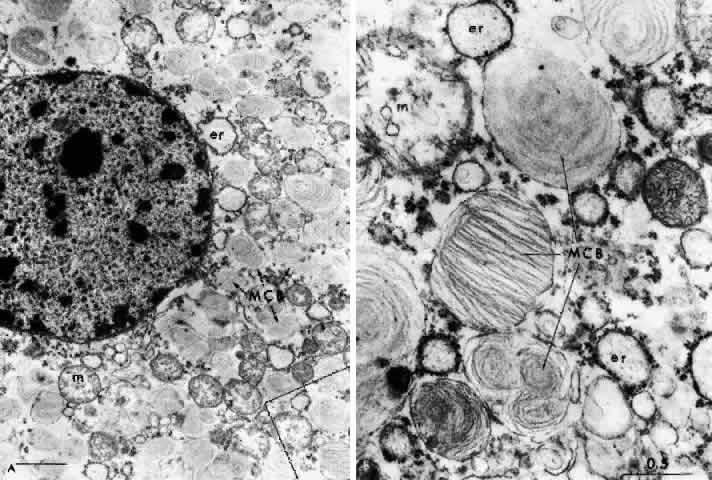

NEUROPATHOLOGY. The pathology in Tay-Sachs disease is diffuse. Intraneuronal storage of GM2-ganglioside occurs in neurons throughout the cortex, brain stem, cerebellum, spinal cord, autonomic ganglia, rectal submucosa, and retina. The affected cells are distended by intralysosomal inclusion bodies composed of closely packed, eccentrically arranged, electron-dense lamellae—the membranous cytoplasmic bodies. The membranous cytoplasmic bodies are characteristic of all the gangliosidoses and represent aggregates of gangliosides and their derivatives with cholesterol and phospholipid, which have oriented to form membranes.

The first histologic study of the eye in Tay-Sachs disease was performed by Collins in 1892.6 Emphasis has since been placed on the staining properties of the storage material, and loss of ganglion cells and extravasation of storage material occurs.7 In Tay-Sachs disease, unlike most other retinal storage diseases, the ganglion cells die early and all of them are involved.

The retinal ganglion cells in the inner portion of the bipolar cell layer and in the inner reticular layer store GM2-ganglioside. As they become affected, the nucleus in the swollen cell locates eccentrically and membranous cytoplasmic bodies fill the cytoplasm; when the cells burst the material is deposited extracellularly without significant phagocytosis or gliosis.

These deposits are strongly birefringent, and striking macular birefringence may be readily visualized in sections of the retina (Fig. 5) even in the unstained state as well as when lightly stained with cresyl violet or sudanophilic dyes.8 Loss of the ganglion cells and atrophy of the optic nerve, which is also evident, are accompanied by a thinning of the nerve fiber layer.

Although ultrastructural studies of the eye have focused primarily on the ganglion cell,8–10 the amacrine cells in the inner nuclear layer of the retina are equally loaded with GM2-ganglioside yet the horizontal cells, bipolar cells, and photoreceptor cells are unaffected.9

NEUROPATHOLOGY. In Sandhoff's disease there is an accumulation of GM2-ganglioside as in Tay-Sachs disease, as well as of asialo-GM2 and GA2-globoside. Ultrastructurally, the metabolic products are stored in almost every tissue as cytoplasmic bodies or cytosomes. These vary in their concentration and configuration, resembling typical membranous cytoplasmic bodies or pleomorphic cytoplasmic inclusions, zebra bodies, vesicles, or granules. Histologic evidence of lipid storage in the viscera is present. Lipid-laden histiocytes appear in the liver and spleen, and there are droplets of fat in the cytoplasm of renal tubular epithelial cells. The accumulation of asialo-GM2-ganglioside is much more marked in CNS tissue and in the liver. Characteristically there is storage also of another glycolipid (a kidney globoside) in the kidney, liver, and spleen as well as in the brain.

There are few reports in the literature describing the ocular pathology of Sandhoff's disease,18–20 but the findings hardly differ from that of Tay-Sachs disease. The major distinctions are the character of the membranous cytoplasmic bodies within the ganglion cells of the retina and the involvement of the cornea. In an electron microscopic study, Brownstein and co-workers2° found abundant pleomorphic storage cytosomes in all neurons of the retina, including the inner segments of the photoreceptor cells, and in astrocytes in the optic nerve.